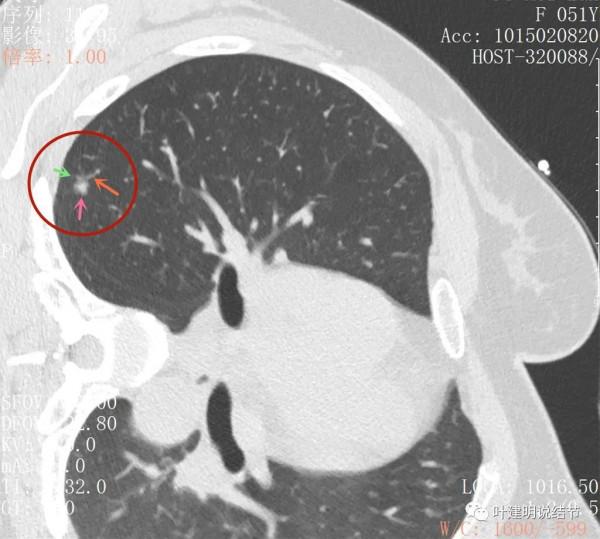

主病灶此層是磨玻璃,但有明顯血管進入病灶(桔色箭頭)

病灶表現不平,密度雜亂,輪廓相對清楚

有明顯的分葉徵(磚色箭頭)以及磨玻璃成分(綠色箭頭)和偏實性的成分(粉紅色箭頭)

上圖也示病灶有明顯的分葉徵(磚色箭頭)以及磨玻璃成分(綠色箭頭)和偏實性的成分(粉紅色箭頭)

上圖層面居然見到病灶周圍的細毛刺徵(紫色箭頭),有實性成分(粉色箭頭)

密度雜亂,輪廓清楚

實性成分較多,有明顯磨玻璃成分

上圖示微血管有血管彎徵,與病灶界限不清,實性成分佔比較高

病灶密度不均,感覺有點僵硬

影象後處理與重建的影象顯示了更清楚的資訊,顯示主病灶(下稱A病灶)分葉(磚色箭頭)、有磨玻璃成分(綠色箭頭)以及實性成分(粉紅色箭頭)

病灶鄰近胸膜,密度雜亂

病灶實性佔比較多,輪廓清楚,胸膜有牽拉(藍色箭頭)

三維重建示病灶圓形類圓形